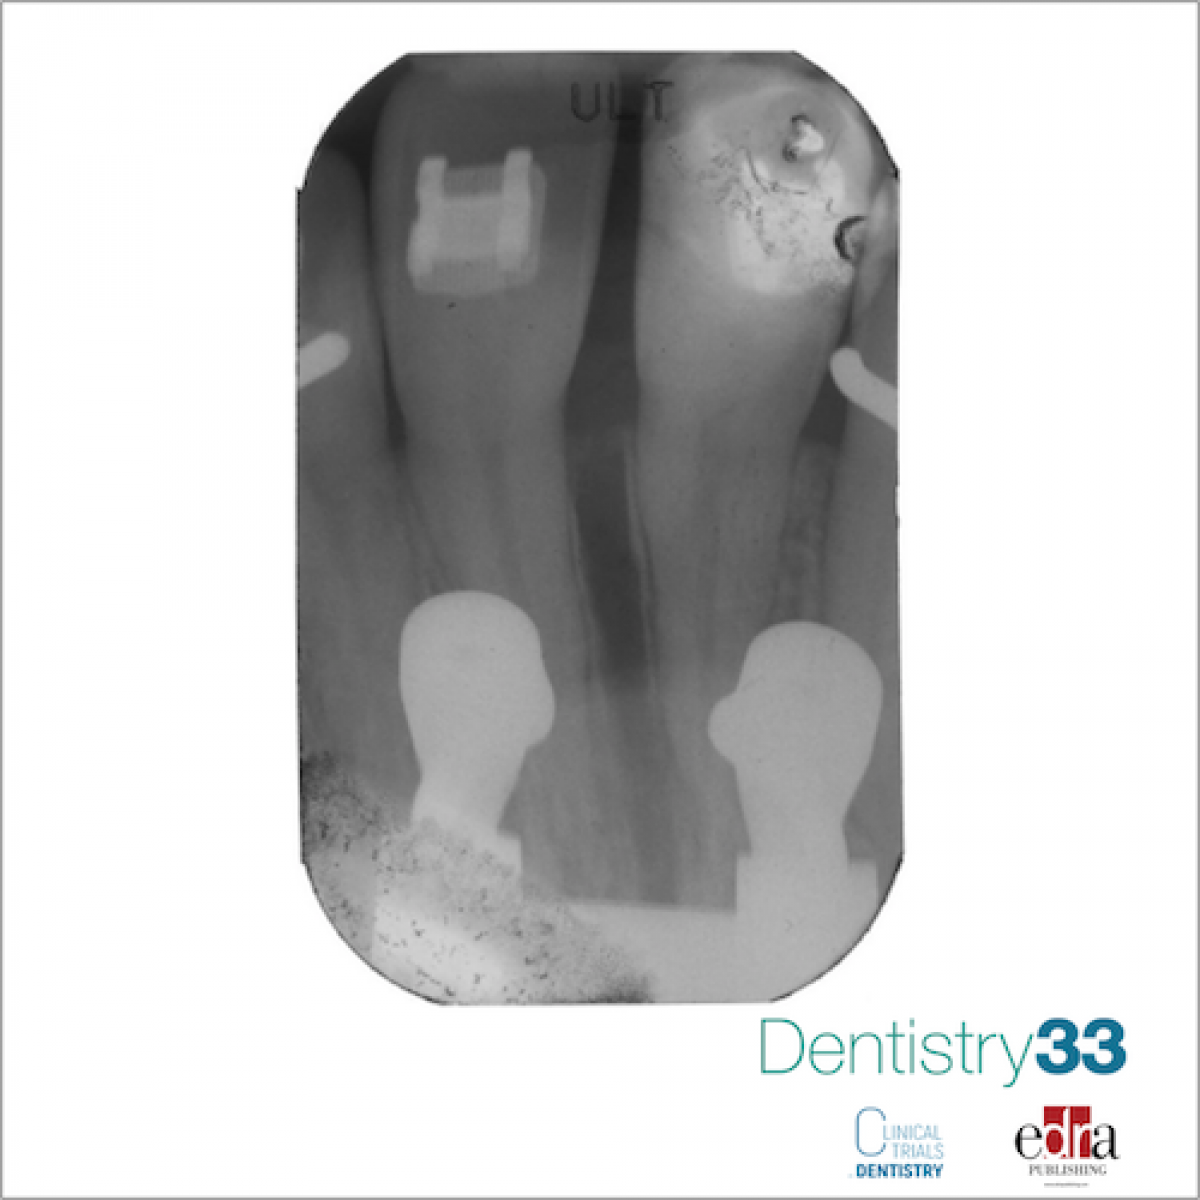

Use of miniscrews in orthodontics: clinical and medical-legal aspects

The technical concepts of anchoring in orthodontics and the opportunity offered to the clinician by the Temporary Anchoring Devices will be analyzed, among which the miniscrews represent the category currently most widespread.

Miniscrews are used more and more frequently in the orthodontic field to temporarily provide direct or indirect skeletal anchorage. They must be used with skill, exploiting their advantageous benefits, without interfering with the bone growth of the young patient and with caution, avoiding the invasion of respectful anatomical structures and the complications related to their possible movement that follows the direction of the orthodontic load. The Italian Clinical Recommendations highlight that the use of miniscrews represents an excellent aid in the control of all dental movements since they constitute a reliable anchor point for the biomechanical management of fixed appliances of all types.